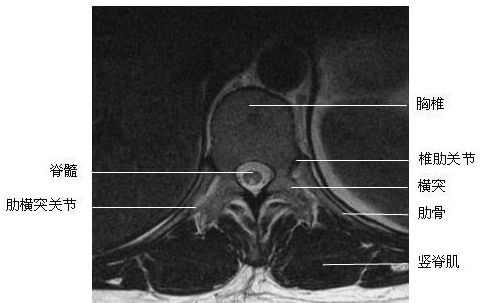

胸段横断面-MRI图